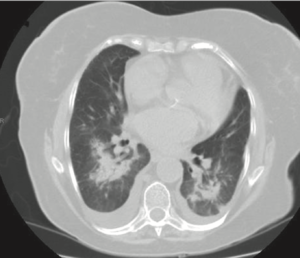

The diagnosis is often clinical and due presence of ground glass opacities of CT in the setting of amiodarone use and after exclusion of an infectious etiology such as pneumonia.

Lung CT Findings

- Ground glass opacities with interstitial or alveolar inflitrations and lung nodules

- Pleural thickening and pleural effusions